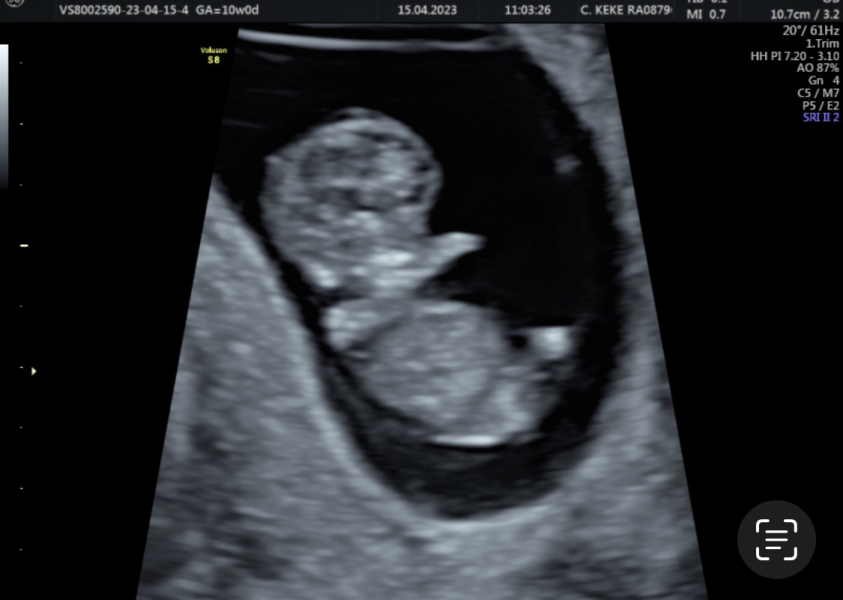

TTCRainbow · 15/04/2023 17:01

10 week scan guys 🥺🥺 feeling so bless and grateful for our little rainbow baby growing 🤍

Awww @TTCRainbow that's a lovely picture 😍

@Sb86 So cute isnt it! I can see a love heart shape in the head too 😭😍Hows everything been with you? xx